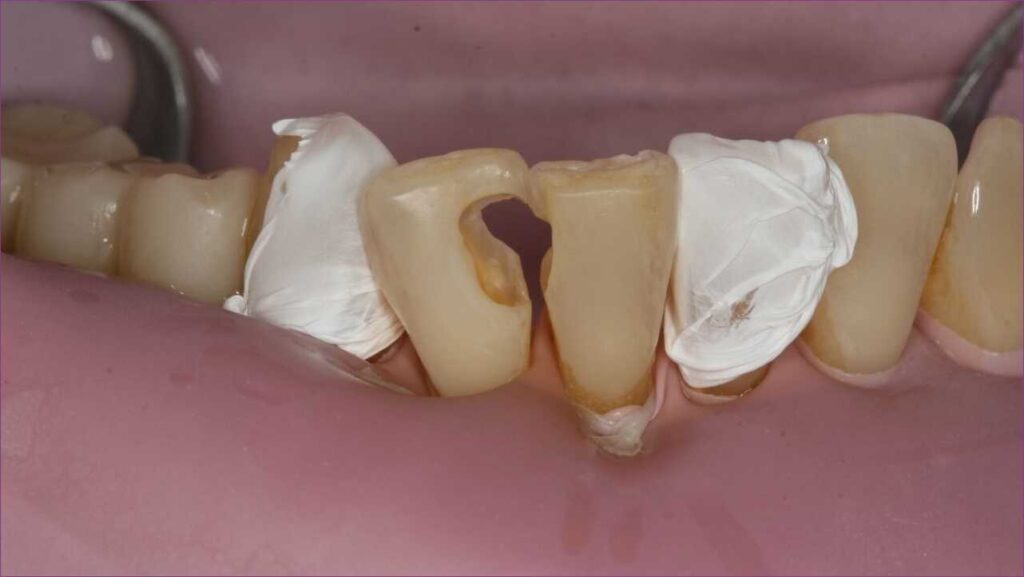

A kompozittömés manapság a legmodernebb és egyben legesztétikusabb tömésfajtának számít. Az anatomikus felépítésnek köszönhetően a fog eredeti funkciója teljes mértékben helyreállítható. A kezelést ezúttal úgynevezett kofferdamizolációban végeztük, mivel a korszerű tömések nagyon érzékenyek a nedvességre. A gondosan elhelyezett gumilepedő távol tartja a nyálat és az egyéb nedvességforrásokat a kezelt területtől. Ráadásul megakadályozza, hogy bármi a torokba kerüljön, például az apró amalgámdarabok.

A stabilitást a tömőanyag kiváló mechanikai tulajdonságai biztosítják, valamint az a tény, hogy a kompozittömés kémiailag kötődik a fog anyagához. A gondos rétegzési technika és a páciens saját fogszínéhez illeszkedő, egyedi festés pedig magas színvonalú esztétikai hatást nyújt: a tömést még nagyítóval sem igen lehet felfedezni!

Hölgypáciensünk roppant elégedett volt a végeredménnyel. Mint a képen is látható, gyakorlatilag eltüntettük a szuvasodás nyomait. Így derűs természetének ismét teret engedhet, vagyis bátran mosolyoghat!